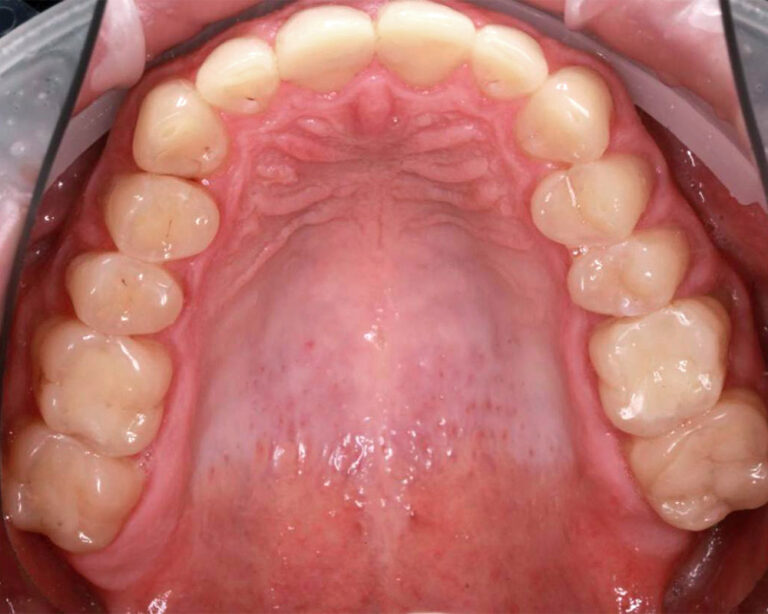

Кейс 12

Бирковская Екатерина Александровна

Количество кап ВЧ 24

Количество кап НЧ 41

ДО

ПОСЛЕ